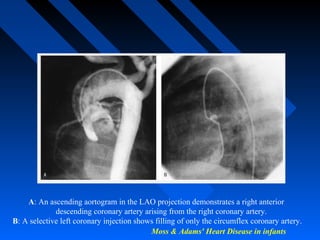

 Coronary artery anatomy … either by aortic root angio,

selective coronary artery injection, or a combination of

both..

Moss & Adams' Heart Disease in infants

A: An ascending aortogram in the LAO projection demonstrates a right anterior

descending coronary artery arising from the right coronary artery.

B: A selective left coronary injection shows filling of only the circumflex coronary artery.

Moss & Adams'Heart Disease in infants A: An ascending aortogram in the LAO projection demonstrates a right anterior descending coronary artery arising from the right coronary artery. B: A selective left coronary injection shows filling of only the circumflex coronary artery.